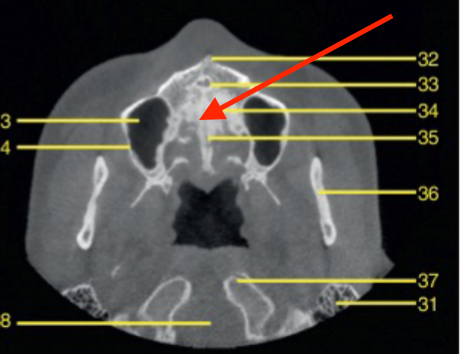

axial

what plane is this

level of maxilla (above maxillary teeth)

at what level is this

mandibular condyle

what structure is this

coronoid process

pterygoid process

identify the structure